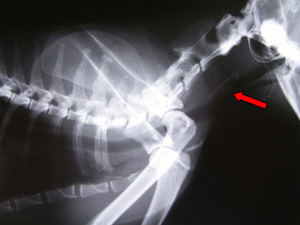

頸部のレントゲン検査の結果、咽頭から頸部食道にかけて骨らしい異物が見られた。

魚の骨が咽頭部に引っかかっていると診断し、麻酔をして長い手術器具を用いて魚の骨を除去した。